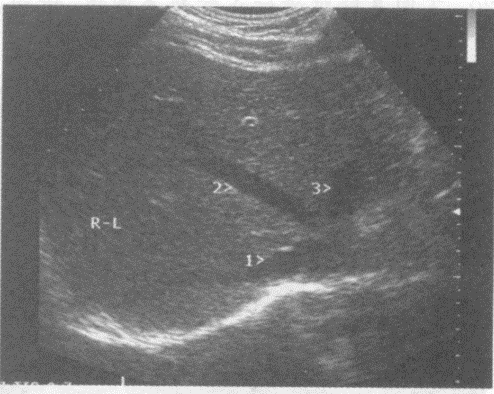

请回答图中1、2、3所指部位的解剖名称()。

A . 1-肝右静脉、2-肝中静脉、3-肝左静脉

B . 1肝左静脉、2-肝中静脉、3-肝右静脉

C . 1-门脉右支、2-肝中静脉、3-门脉左支

D . 1-门脉右后支、2-门脉右前支、3-门脉左支